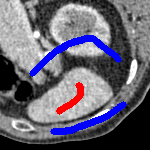

The motivation for this work comes from observing contradictions in using piecewise-constant intensity fitting terms in selective segmentation. Whilst good results are possible with this approach, the exceptional cases lead to severe limitations in practice. This is quite common in medical imaging as demonstrated in Fig. 1, where the target foreground has a low intensity. Given that the corresponding background includes large regions of low intensity, the optimal average intensities for this segmentation problem are and . For cases where , we see that by (1), almost everywhere in the domain . This means that it is very difficult to achieve an adequate result, without an over-reliance on the user input or parameter selection.

| (10) |

for and as defined in (33). This is consistent with respect to the intensities of the observed object and the concept of selective segmentation. In Fig. 3 we see the difference between CV and the proposed fitting terms for given user input on a CT image. For the CT image, the CV fitting terms are near 0 within the target region. This is despite there being a distinct homogeneous area with good contrast on the boundary. This illustrates the problem we are aiming to overcome. With the proposed fitting term this phenomenon should be avoided in cases like this. By defining as in (33) there is no contradiction if the foreground and background intensities of the target region are similar.